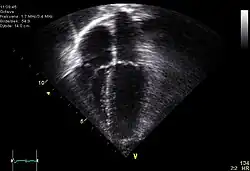

Le cœur est un organe intra thoracique, entouré d'air (les poumons) et d'os (les côtes). Ces deux dernières structures ne laissent pas transmettre les ultrasons, rendant l'examen plus complexe. On se sert ainsi d'un nombre limité de « fenêtres » anatomiques, lieux où le cœur peut être visualisé par l'échocardiographie, sans interposition aérienne ou osseuse.

Le cœur est un organe tridimensionnel mobile. La prise en compte de cette quatrième dimension (le temps) est nécessaire pour une bonne appréhension de l'organe dans sa globalité. Cela nécessite une résolution temporelle suffisante pouvant être caractérisée par la cadence d'acquisition des images : elle doit être au moins d'une vingtaine images/s et idéalement supérieure à 50 images/s (pour permettre une visualisation correcte en ralenti, surtout si la fréquence cardiaque est élevée). De même, l'analyse à l'aide d'une image, par essence, bidimensionnelle, d'un organe quadridimensionnel, impose certains artifices : c'est le mode Tm (pour l' anglais : time motion), utilisé de manière courante, avec en abscisse le déroulement du temps et en ordonnée les échos détectés sur une seule ligne de tir.

- Le cœur est un organe tridimensionnel battant. L'échocardiographie effectue des coupes de cet organe et les résultats peuvent varier suivant le plan de coupe choisi. L'examen reste dépendant de l'expérience de l'examinateur.

Échographie tridimensionnelle

Par le biais d'un capteur non plus linéaire, mais matriciel, une imagerie tridimensionnelle directe est possible. Cette technique relativement nouvelle (la sonde matricielle étant disponible à relativement grande échelle depuis 2002), est en cours d'évaluation.